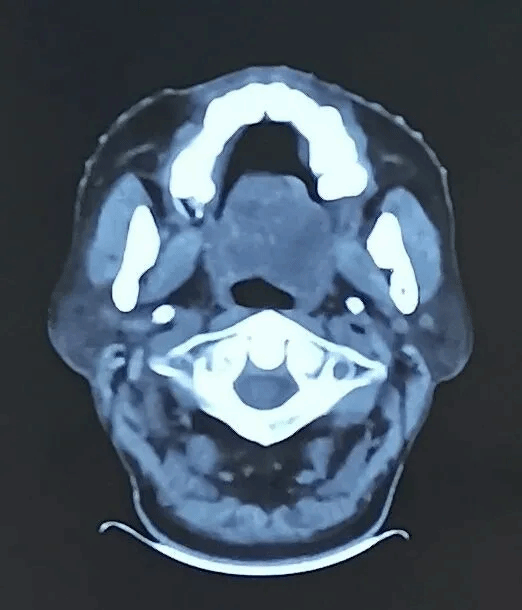

治疗前

渴望收获安稳睡眠的路先生辗转来到我院放疗科就诊。科室团队迅速启动多学科会诊,针对肿瘤体积大、位置特殊、紧邻重要器官的复杂情况,制定了个体化精准放疗方案。借助先进的影像及放疗技术,团队精准勾勒肿瘤靶区,将高剂量射线精准聚焦于病灶,在最大限度保护周围正常组织的同时,对肿瘤展开集中“攻坚”。